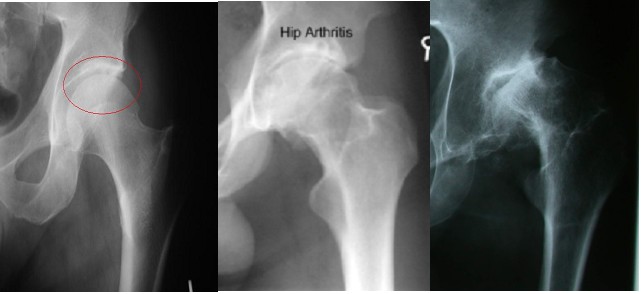

Standing x-rays of the hip joint will give a good assessment of remaining joint space and bone changes related to arthritis:

A simple x-ray should show changes of osteoarthritis. The x-ray findings classically include as joint space narrowing, subarticular sclerosis, osteophytes and degenerative cyst formation.

The articular surfaces of the hip can be assessed by contrast MRI arthrography[1]. However there is no widely accepted system for MRI grading of chondral loss in the hip joint. Many have used a modification of the Outerbridge classification and applied to named parts of the joint. In the future a system based upon the percentage volume of lost cartilage may be most appropriate.